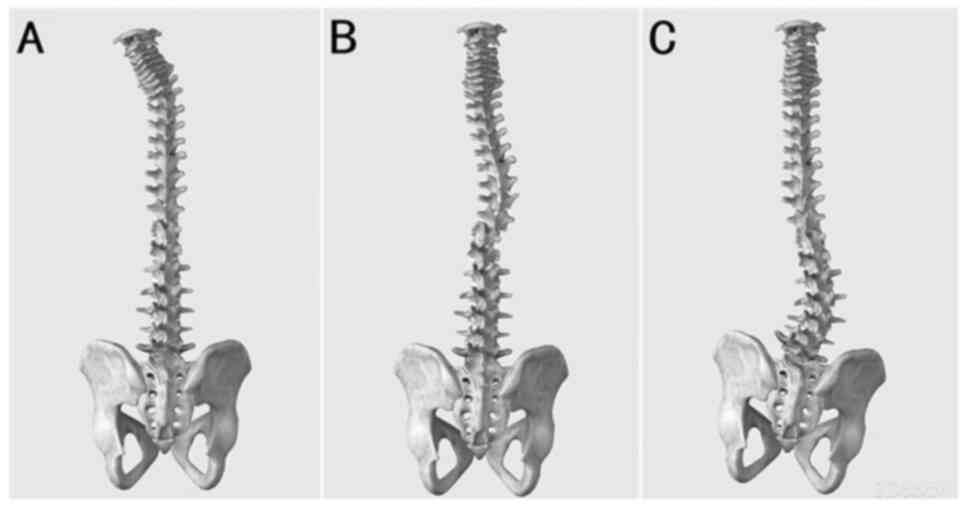

Morphologically, the vertebral bodies of idiopathic scoliosis line

up similarly to a ‘c’ shape, whereas the vertebral bodies of

astrocytoma-induced scoliosis in the present study lined up

similarly to an ‘L’ shape with a larger angle. The morphology of

this scoliosis type in the cervical, thoracic and lumbar spine is

shown in Fig. 2.